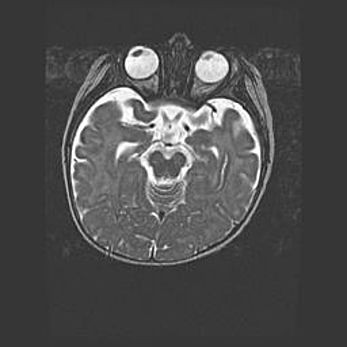

Церебральная ишемия II.

Возраст: 5 дней

Вес: 3400 г

Пол: женский

Окружность головы: 35 см

Срок гестации: 39 недель

Церебральная ишемия – это заболевание, характеризующееся недостаточностью (гипоксией) либо полным прекращением (аноксией) снабжения мозга кислородом по причине закупорки одного или нескольких сосудов. Это приводит к  что метаболическим расстройствам различной степени тяжести в тканях головного мозга, развитию коагуляционных некрозов и гибели нейронов.